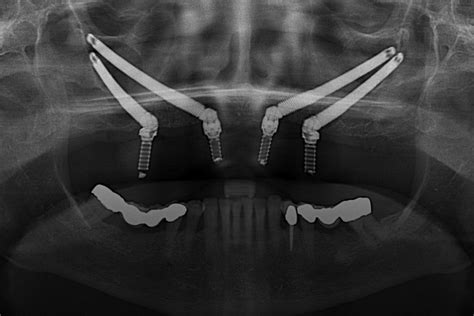

La planificación de los implantes en cuanto a sus dimensiones y posiciones tuvo lugar virtualmente mediante el software Procera (NobelGuide, Nobel Biocare). En el maxilar superior estaban previstos 12 implantes. Con vistas a esta intervención se diseñaron y fueron requeridas por el fabricante dos plantillas quirúrgicas.

Después de recibir las plantillas quirúrgicas (NobelGuide) del fabricante, se confeccionaron modelos maestros de las plantillas mediante los cilindros de guía, los cuales mantenían en posición los implantes de manipulación.

En el maxilar inferior se recurrió al protocolo NobelGuide convencional para la elaboración del modelo maestro en el marco de la implantación. La plantilla quirúrgica fue provista de implantes de manipulación. Para la reducción del perfil de emergencia se utilizaron cofias de transferencia con diámetro reducido.